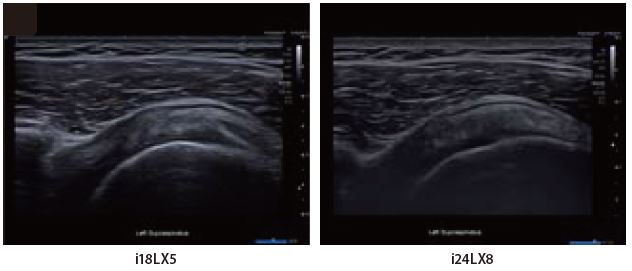

Це парні зображення пацієнта з гіпотиреозом і множинними напівкістозними/твердими вузлами.

Обидва датчики i-серії добре окреслюють внутрішні структури вузлів щитоподібної залози. Однак у датчика i24LX8 контур і межі меншого вузла чіткіші, і навіть при роботі на дуже високій частоті не відбувається втрати проникаючої здатності. Краща клінічна деталізація може допомогти в діагностиці та поліпшити класифікацію вузлових утворень щитоподібної залози.

Мал. 8.